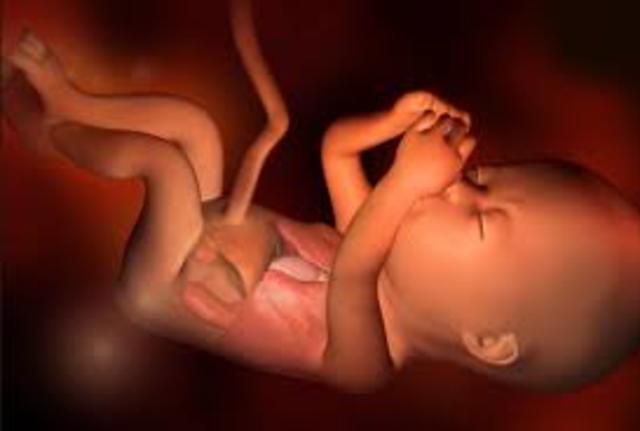

Su sistema nervioso es capaz de controlar los moviemientos respiratorios y la temperatura. Sus movimientos son mas activos.Su estomago, intestinos y riñones funcionan perfectamente. Todos sus organos sensoriales estan despieros, los parpados y los ojos estan completamente formados y comienzan a abrirse y cerrarse, Empieza a percibir los sonidos, los ruidos intensos le aumentan la frecuencia cardiaca. Llega a tener hipo.

• Semana 30 a la 38

Semana 30 a la 38

Ya se encuentra en posicion adecuada para el momento del parto en la mayoria de los casos es con la cabeza hacia abajo y los gluteos hacia ariba. Su craneo todavia no sta totalmente solido, ya que necesita pasar por el canal de parto.Desliza su pulgar dentro de su boca y practica el reflejo de la succion. Al final de este periodo el bebe puede alcanzar una talla de hasta 50 cm y un peso promedio de 3kg. Hacia el final de la semana 38, el bebe esta en condiciones de nacer.